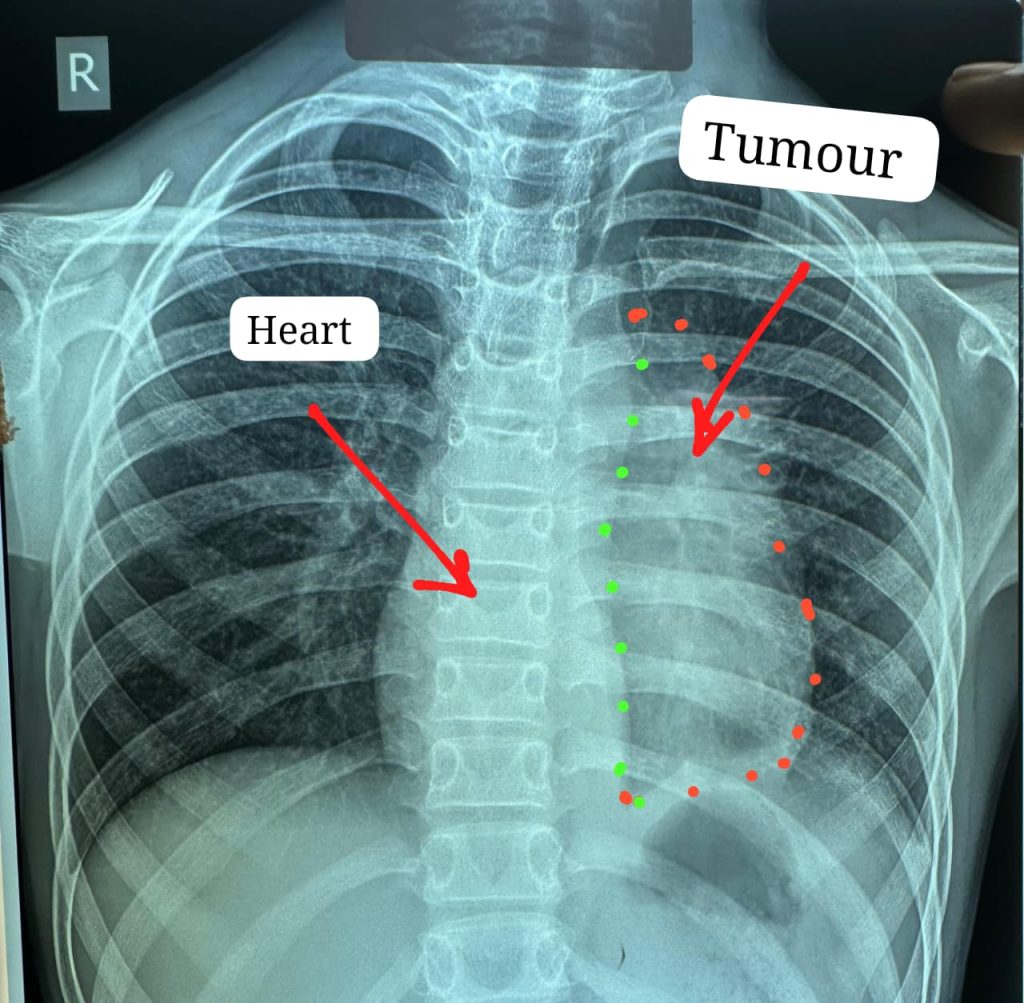

चिकित्सा क्षेत्र की एक ऐतिहासिक उपलब्धि सामने आई है, जहाँ डॉक्टरों की टीम ने 11 साल के एक बच्चे के दिल से चिपका अत्यंत दुर्लभ कैंसर सफलतापूर्वक निकालकर न केवल उसकी जान बचाई, बल्कि एक संभावित विश्व कीर्तिमान भी स्थापित किया है। यह जटिल सर्जरी कई घंटों तक चली, जिसमें हृदय के बेहद संवेदनशील हिस्से से ट्यूमर को बिना किसी बड़े नुकसान के अलग करना सबसे बड़ी चुनौती थी।

डॉक्टरों के अनुसार, इस प्रकार का कैंसर दिल से इस स्तर पर चिपका होना अत्यंत दुर्लभ होता है और विश्व में ऐसे मामले बहुत कम दर्ज हैं। ऑपरेशन के दौरान उच्च स्तरीय तकनीक और विशेषज्ञता का उपयोग किया गया, जिससे बच्चे की स्थिति अब स्थिर बताई जा रही है।